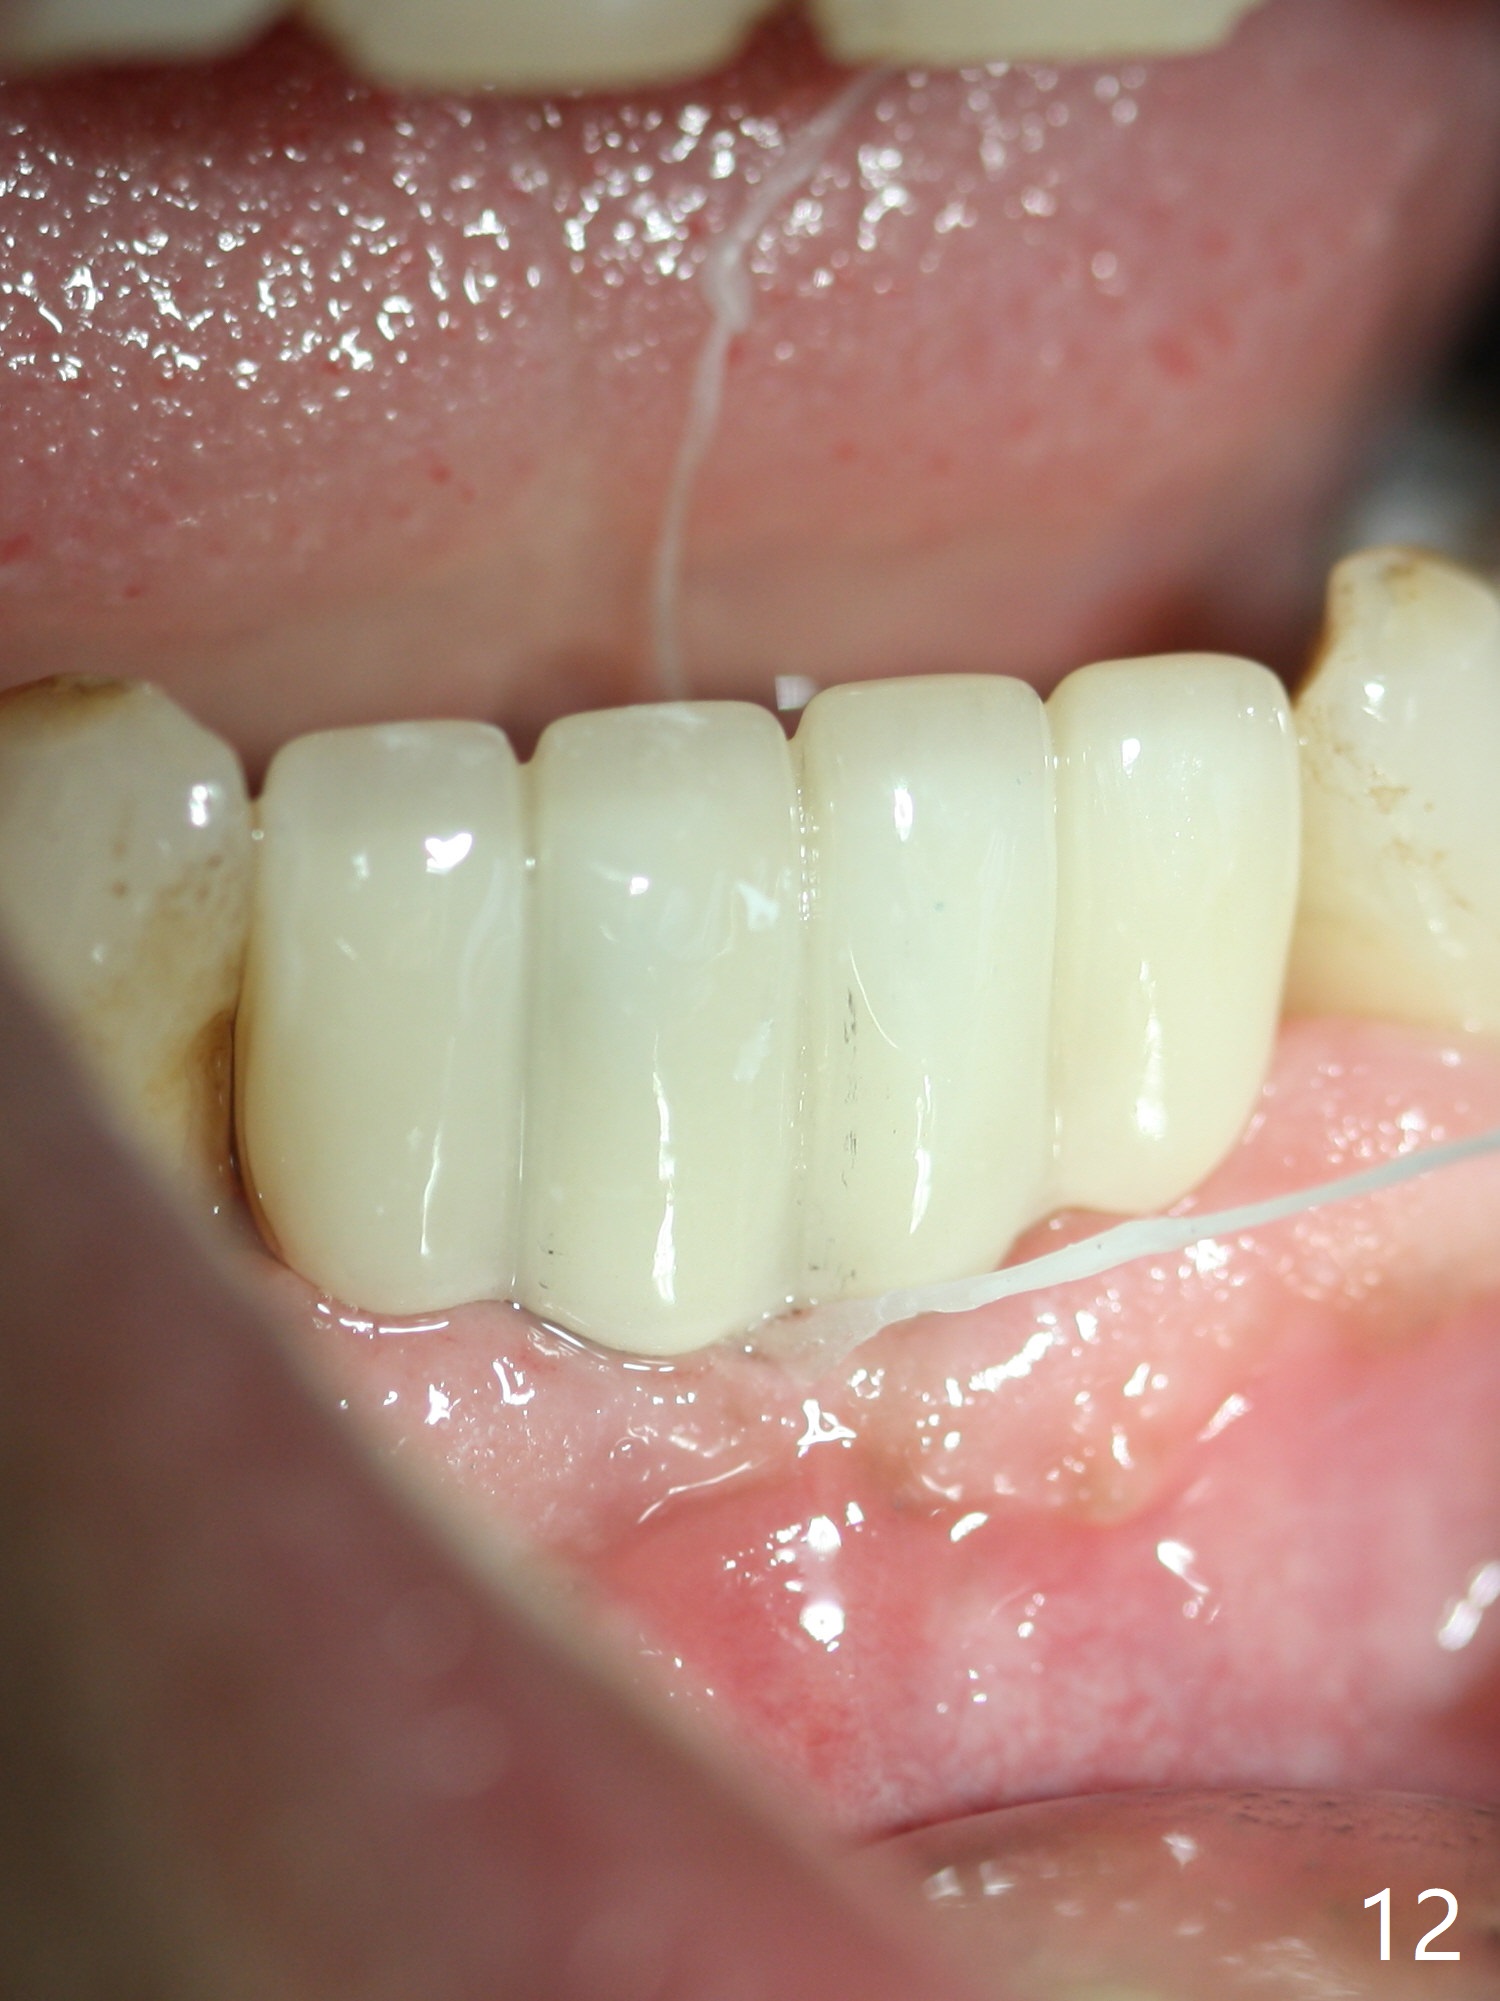

When the patient (smoker) returns for treatment, the apical abscess associated with #25 and 26 reduces with oral Amoxicillin. He agrees with 4 incisor extraction because of 2 apical fistulae (Fig.1 >). Osteotomy starts at the central incisor sockets due to mesial root exposure of the canines (Fig.2 arrowheads) and buccal alveolar bone fracture between #23 and 24 (Fig.7). Two of 3x14(4) mm 1-piece implants are placed with ~ 2 mm buccal gap (Fig.3). After Vanilla graft is placed in the bony defects (Fig.5 *) and Osteogen plug, sutures are placed (Fig.4). The implants are then placed deep to decrease thread exposure (Fig.6). Periodontal dressing is applied instead of provisional. Alveolar bone fracture between #23 and #24 accounts for why an implant is less suitably placed at #24 (Fig.7). Three months postop, composite is added to the pontic areas of the provisional (Fig.8 *). When the provisional is seated, the convex pontics press the used-to-be-flat gingiva (Fig.9 arrows). Thus the concave gingiva forms (Fig.10 *) with corresponding papillae (^). In fact the photos of Fig.8-10 is taken ~3 weeks later. Most of the grafted bone remains in place 3.5 months postop (Fig.11). A piece of floss with 2 knots in one end is placed between the middle units of the final bridge before cementation (Fig.12 (4 months 10 days postop)). In fact removal of residual cement is not so simple. It is tedious (Fig.13,14). An asymptomatic buccal fenetration with implant thread exposure is found 2 months post cementation and persists for another month in spite of advice to reduce smoking (1/2 ppd) and use of water pik (Fig.15). The area will be debrided, followed by bone graft and PRF in a month.